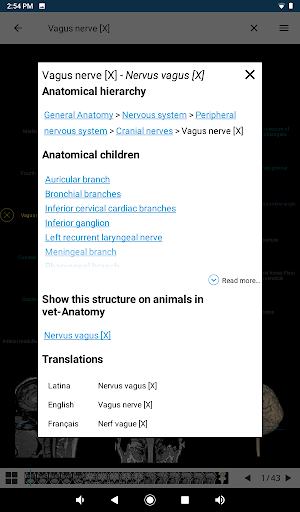

. *Navegación entre partes anatómicas usando enlaces de descripción.

la vista de detalles de una estructura anatómica ahora se muestran los términos relacionados

-Dentro de la vista de detalles de una estructura anatómica , un alfiler ahora señala la estructura relacionada en todas las imágenes presentes